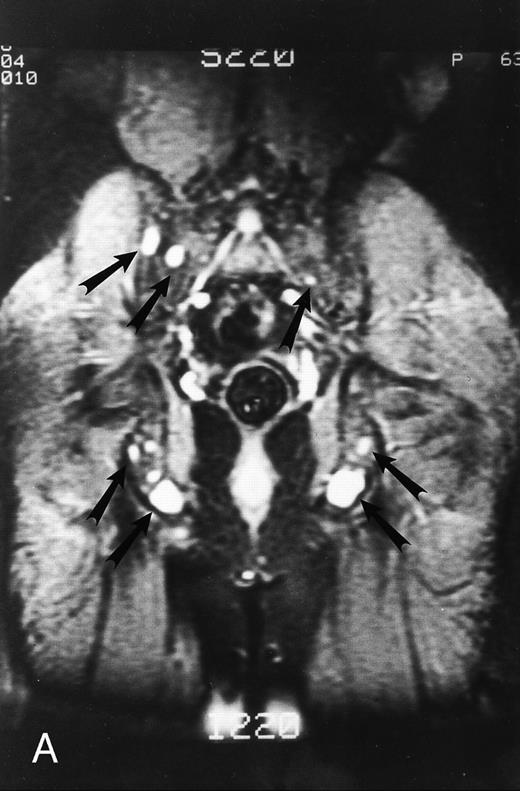

A 75-year-old woman with Waldenstrom macroglobulinemia: T1-weighted (600/20, TR/TE) axial (A) and sagittal T1-weighted (600/20, TR/TE) precontrast (B) and postcontrast (C) MR images of the lumbosacral spine. Note diffuse pattern of marrow infiltration and enlarged retroperitoneal lymph nodes (arrows). The abnormal marrow is isointense to the intervertebral discs on the precontrast image and enhances markedly becoming hyperintense to the discs on the postcontrast image.